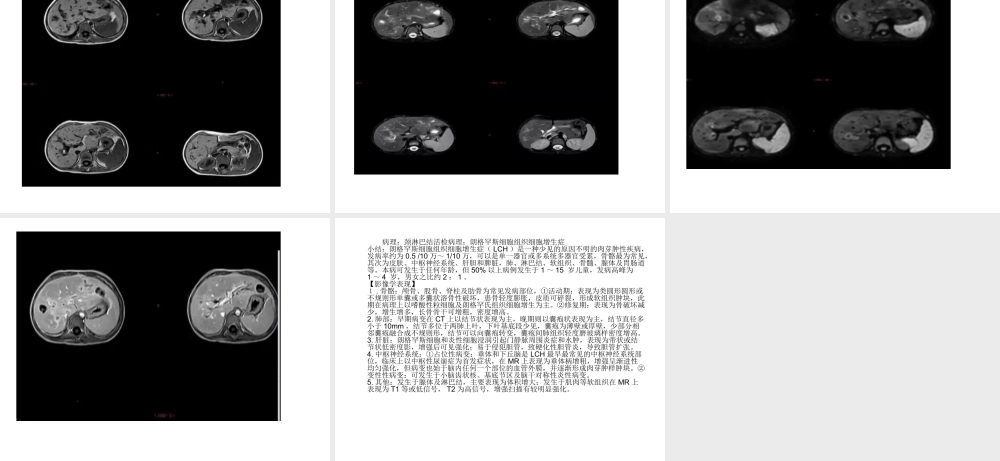

病例分析影像表现病理:颈淋巴结活检病理:朗格罕斯细胞组织细胞增生症小结:朗格罕斯细胞组织细胞增生症(LCH)是一种少见的原因不明的肉芽肿性疾病,发病率约为0.5/10万~1/10万,可以是单一器官或多系统多器官受累,骨骼最为常见,其次为皮肤、中枢神经系统、肝胆和脾脏,肺、淋巴结、软组织、骨髓、腺体及胃肠道等。本病可发生于任何年龄,但50%以上病例发生于1~15岁儿童,发病高峰为1~4岁,男女之比约2:1。【影像学表现】1.骨骼:颅骨、股骨、脊柱及肋骨为常见发病部位,①活动期:表现为类圆形圆形或不规则形单囊或多囊状溶骨性破坏,患骨轻度膨胀,皮质可碎裂,形成软组织肿块,此期在病理上以嗜酸性粒细胞及朗格罕氏组织细胞增生为主。②修复期:表现为骨破坏减少,增生增多,长骨骨干可增粗,密度增高。2.肺部:早期病变在CT上以结节状表现为主,晚期则以囊疱状表现为主,结节直径多小于10mm,结节多位于两肺上叶,下叶基底段少见,囊疱为薄壁或厚壁,少部分相邻囊疱融合成不规则形,结节可以向囊疱转变,囊疱间肺组织轻度磨玻璃样密度增高。3.肝脏:朗格罕斯细胞和炎性细胞浸润引起门静脉周围炎症和水肿,表现为带状或结节状低密度影,增强后可见强化;易于侵犯胆管,致硬化性胆管炎,导致胆管扩张。4.中枢神经系统:①占位性病变:垂体和下丘脑是LCH最早最常见的中枢神经系统部位,临床上以中枢性尿崩症为首发症状,在MR上表现为垂体柄增粗,增强呈渐进性均匀强化,但病变也始于脑内任何一个部位的血管外膜,并逐渐形成肉芽肿样肿块。②变性性病变:可发生于小脑齿状核、基底节区及脑干对称性炎性病变。5.其他:发生于腺体及淋巴结,主要表现为体积增大;发生于肌肉等软组织在MR上表现为T1等或低信号,T2为高信号,增强扫描有较明显强化。